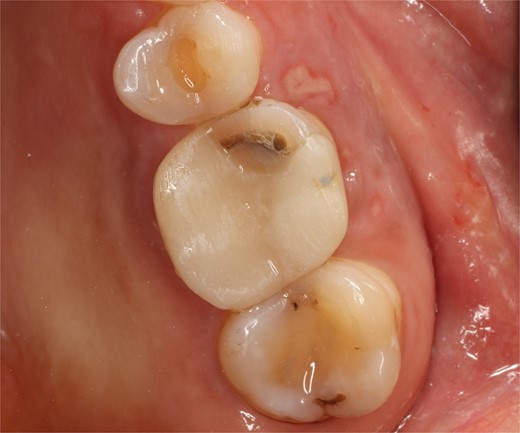

A 56-year-old female patient without any systemic diseases was referred by otolaryngology for evaluation by oral surgery due to presenting pain on the left side of the face for two weeks. The patient’s first molar presented a wide restoration (Fig. 1). This molar had undergone endodontic treatment some years ago. The CT scan showed a hyperdense left maxillary sinus almost entirely with loss of continuity of the maxillary sinus floor at the level of the left upper first molar involving the furcation zone, it is evident an oroantral communication of 7 mm (Fig. 2). The patient referred to spontaneous pain during chewing. Based on the CT scan and the clinical findings, pharmacological management was indicated with oral antihistamine 10 mg every 24 hours for 10 days, Moxifloxacin 400 mg every 24 hours, and scheduled extraction with oroantral communication closure with collagen sponge on the third day after starting the antibiotic, which will be used for a total of 10 days. The patient agreed to sign an informed consent file to make the technique to extraction and close the oroantral communication.